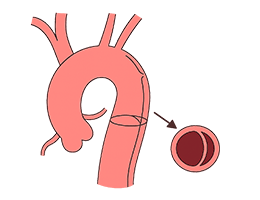

대동맥박리 (Aortic dissection)